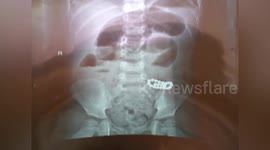

Doctor in China removes toothpicks, cotton swabs and pencils from boy's body

A doctor removed 30 toothpicks, 24 cotton swabs and five pencils from a nine-year-old boy's body in southern.

The video, filmed in the city of Qinzhou in Guangxi Zhuang Autonomous Region on March 13, shows something getting stuck in the boy's gastrointestinal tract in the x-ray picture.

The doctor named Yang Lijian had an over four-hour surgery for the boy to take out more than 30 toothpicks, 24 cotton swab, five pencils and other items.

Fortunately, the boy is recovering well and started to have soup and congee.